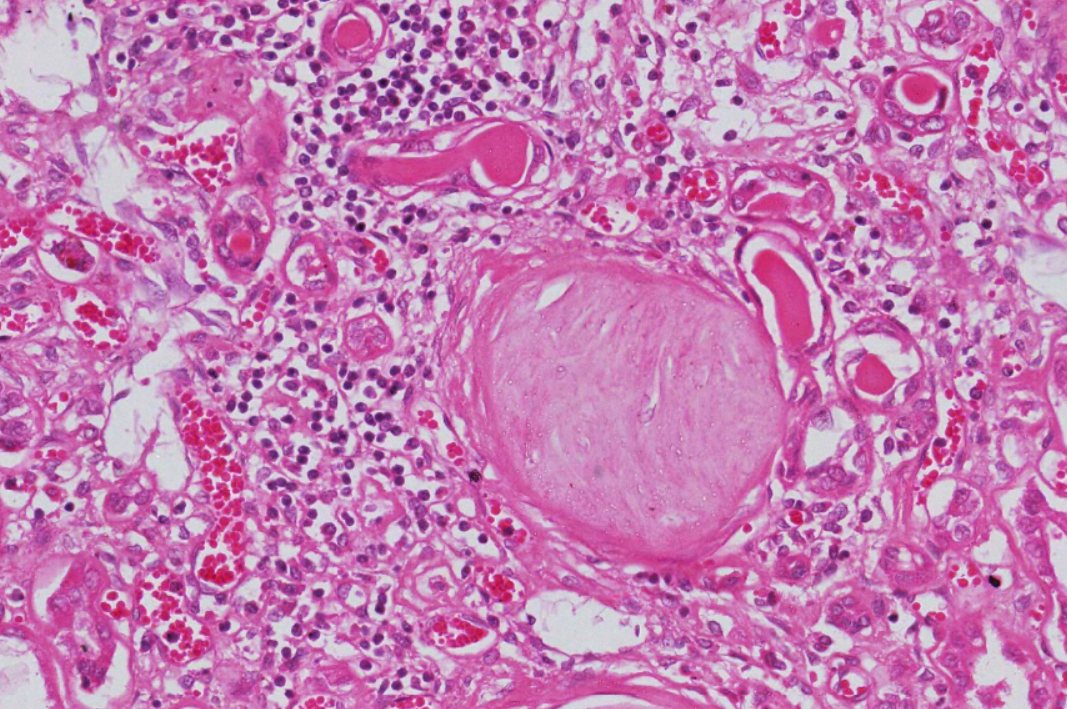

糖尿病肾病:1.大部分肾小球系膜区大量基质增多,较多形成结节状扩大,少数细胞靠结节边缘排列, 形成典型的K-W结节。部分节段有系膜细胞轻度增生, 基膜增厚。2.少数小球伴有球囊壁纤维化。 少部分肾小球硬化(玻璃样小体)。3.肾小管较多灶性萎缩,部分肾小管扩张,管腔内有蛋白管型。4.间质广泛纤维化,伴大量炎症细胞浸润(淋巴细胞、浆细胞)。许多肾小球入球细动脉壁增厚玻变, 间质肌性小动脉内膜增厚纤维化。

2.肾小球多个W-K结节形成